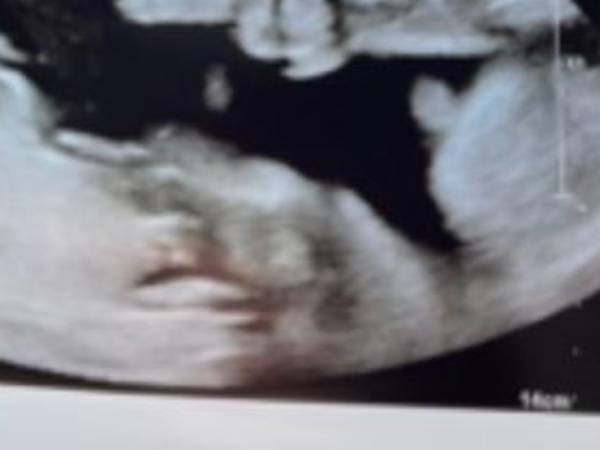

なぜなら…赤ちゃんが胎内でピースサインをしていたからです!

まるで「ママ、パパ、こっちはいい感じよ!」というように、バッチリとピースが見えますね。

ちなみにアビゲイルさんがシェアした、1枚目のエコー写真がこちらです。

この写真が撮れた直後に、検査技師が手と腕がよりはっきり見える写真を撮ったそうです。